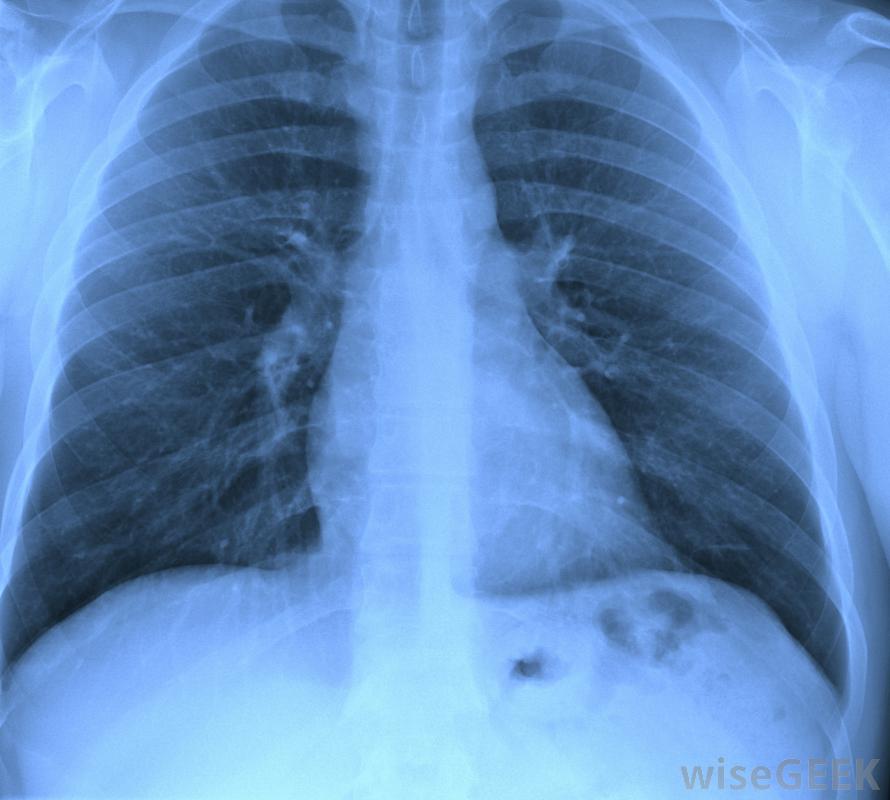

一些天花板瓷砖含有石棉。另一种健康状况是最常见的石棉危害之一是肺癌。肺癌通常是致命的。肺癌的总体五年生存率1995年至2002年的癌症发病率仅为15%,接触石棉而形成胸膜斑的人患肺癌的风险比不接触石棉的人高,胸膜斑是在壁上形成的疤痕组织带由于吸入石棉纤维,吸入的石棉纤维被困在肺部并积聚,造成肺部疤痕并导致呼吸困难。石棉肺是一种因吸入石棉而引起的肺部炎症性疾病。它会导致咳嗽、气短,以及永久性肺损伤。石棉肺可以发展多年而无症状,尽管x光可以在早期发现石棉暴露对肺的损害。根据国际癌症研究机构的报告,石棉肺的相关研究危害已经显示出足够的证据表明接触石棉的人患胃肠道癌和喉癌的风险增加。接触石棉的人患喉癌、食道癌、结肠癌的风险更大,在一些研究中,与石棉危害有关的其他癌症包括卵巢癌和肾癌虽然这些研究没有提供足够的证据证明石棉暴露与这些癌症的诊断直接相关,接触石棉的人患喉癌的风险更大。